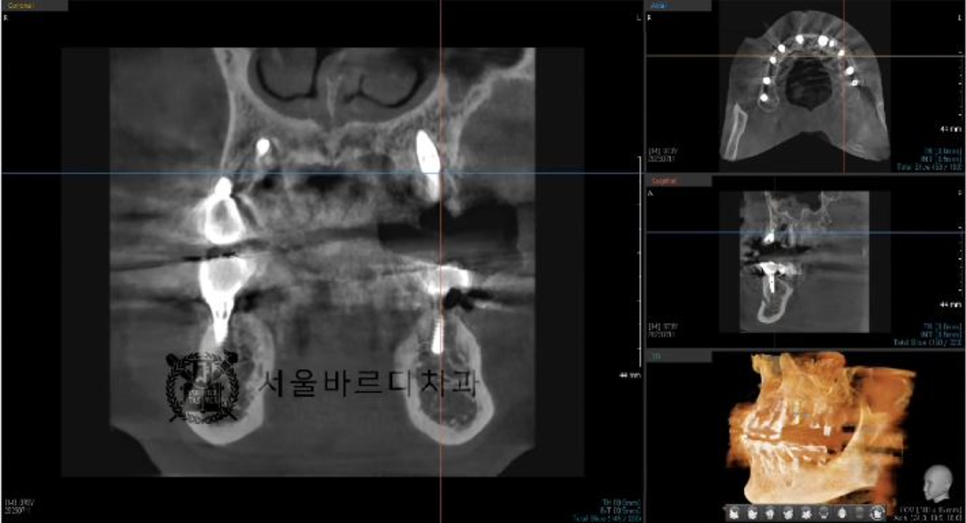

정확한 뼈 상태태를 확인하기 위해 수술전에

3D CT와 구강스캔데이터를 가지고 모의 수술을 해 본 후에

시뮬레이션 결과대로 임플란트 수술을 할 수 있게 하는

가이드 장치를 제작합니다

맞춤 장치를 제작하는 네비게이션 임플란트라고 하는데요.

더 안전하고 정확한 임플란트 수술을 위한 작업입니다.

20230711

빠진 임플란트와 그 옆에 하나 더 임플란트 시술을 하셨습니다.

임플란트 후에도 수술이 잘 되었는지

파노라마와 3D CT촬영으로 결과를 확인합니다.